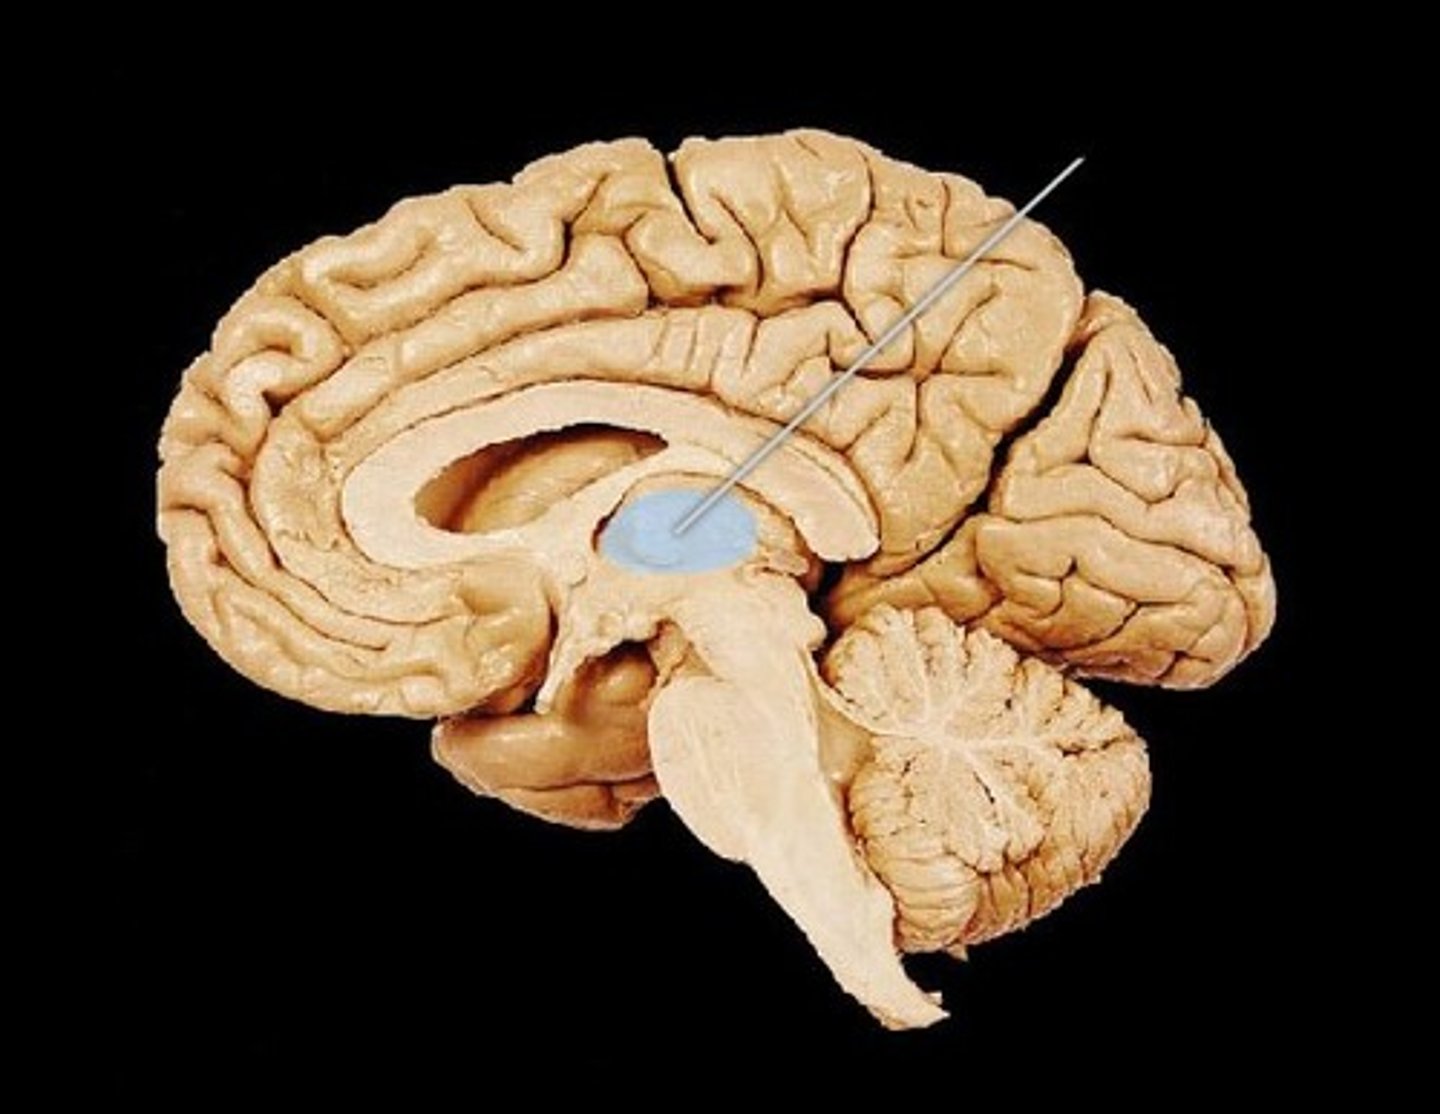

thalamus

the brain's sensory control center, located on top of the brainstem; it directs messages to the sensory receiving areas in the cortex and transmits replies to the cerebellum and medulla; handles all sense except smell

amygdala

found in the Limbic System; Controls aggression & emotional impulses/fear & anger (consists of two lima bean-sized neural clusters )

hypothalamus

a neural structure lying below (hypo) the thalamus; it directs several maintenance activities (eating drinking body temperature), helps govern the endocrine system via the pituitary gland, and is linked to emotion and reward.

Hippocampus

found in the Limbic System; handles learning and memory; specially the formation of NEW memories

basal ganglia

inner structure of the brain handling fine motor & voluntary movements (not part of limbic system)